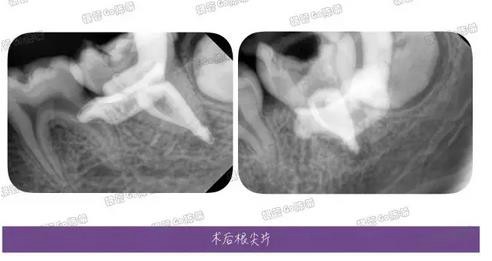

完成充填后的多角度根尖片,檢查根充效果,之前有幾個病例糊劑超填得明顯,所以做了一定的改正。

這例看來是控制得稍微好點了,繼續(xù)努力~